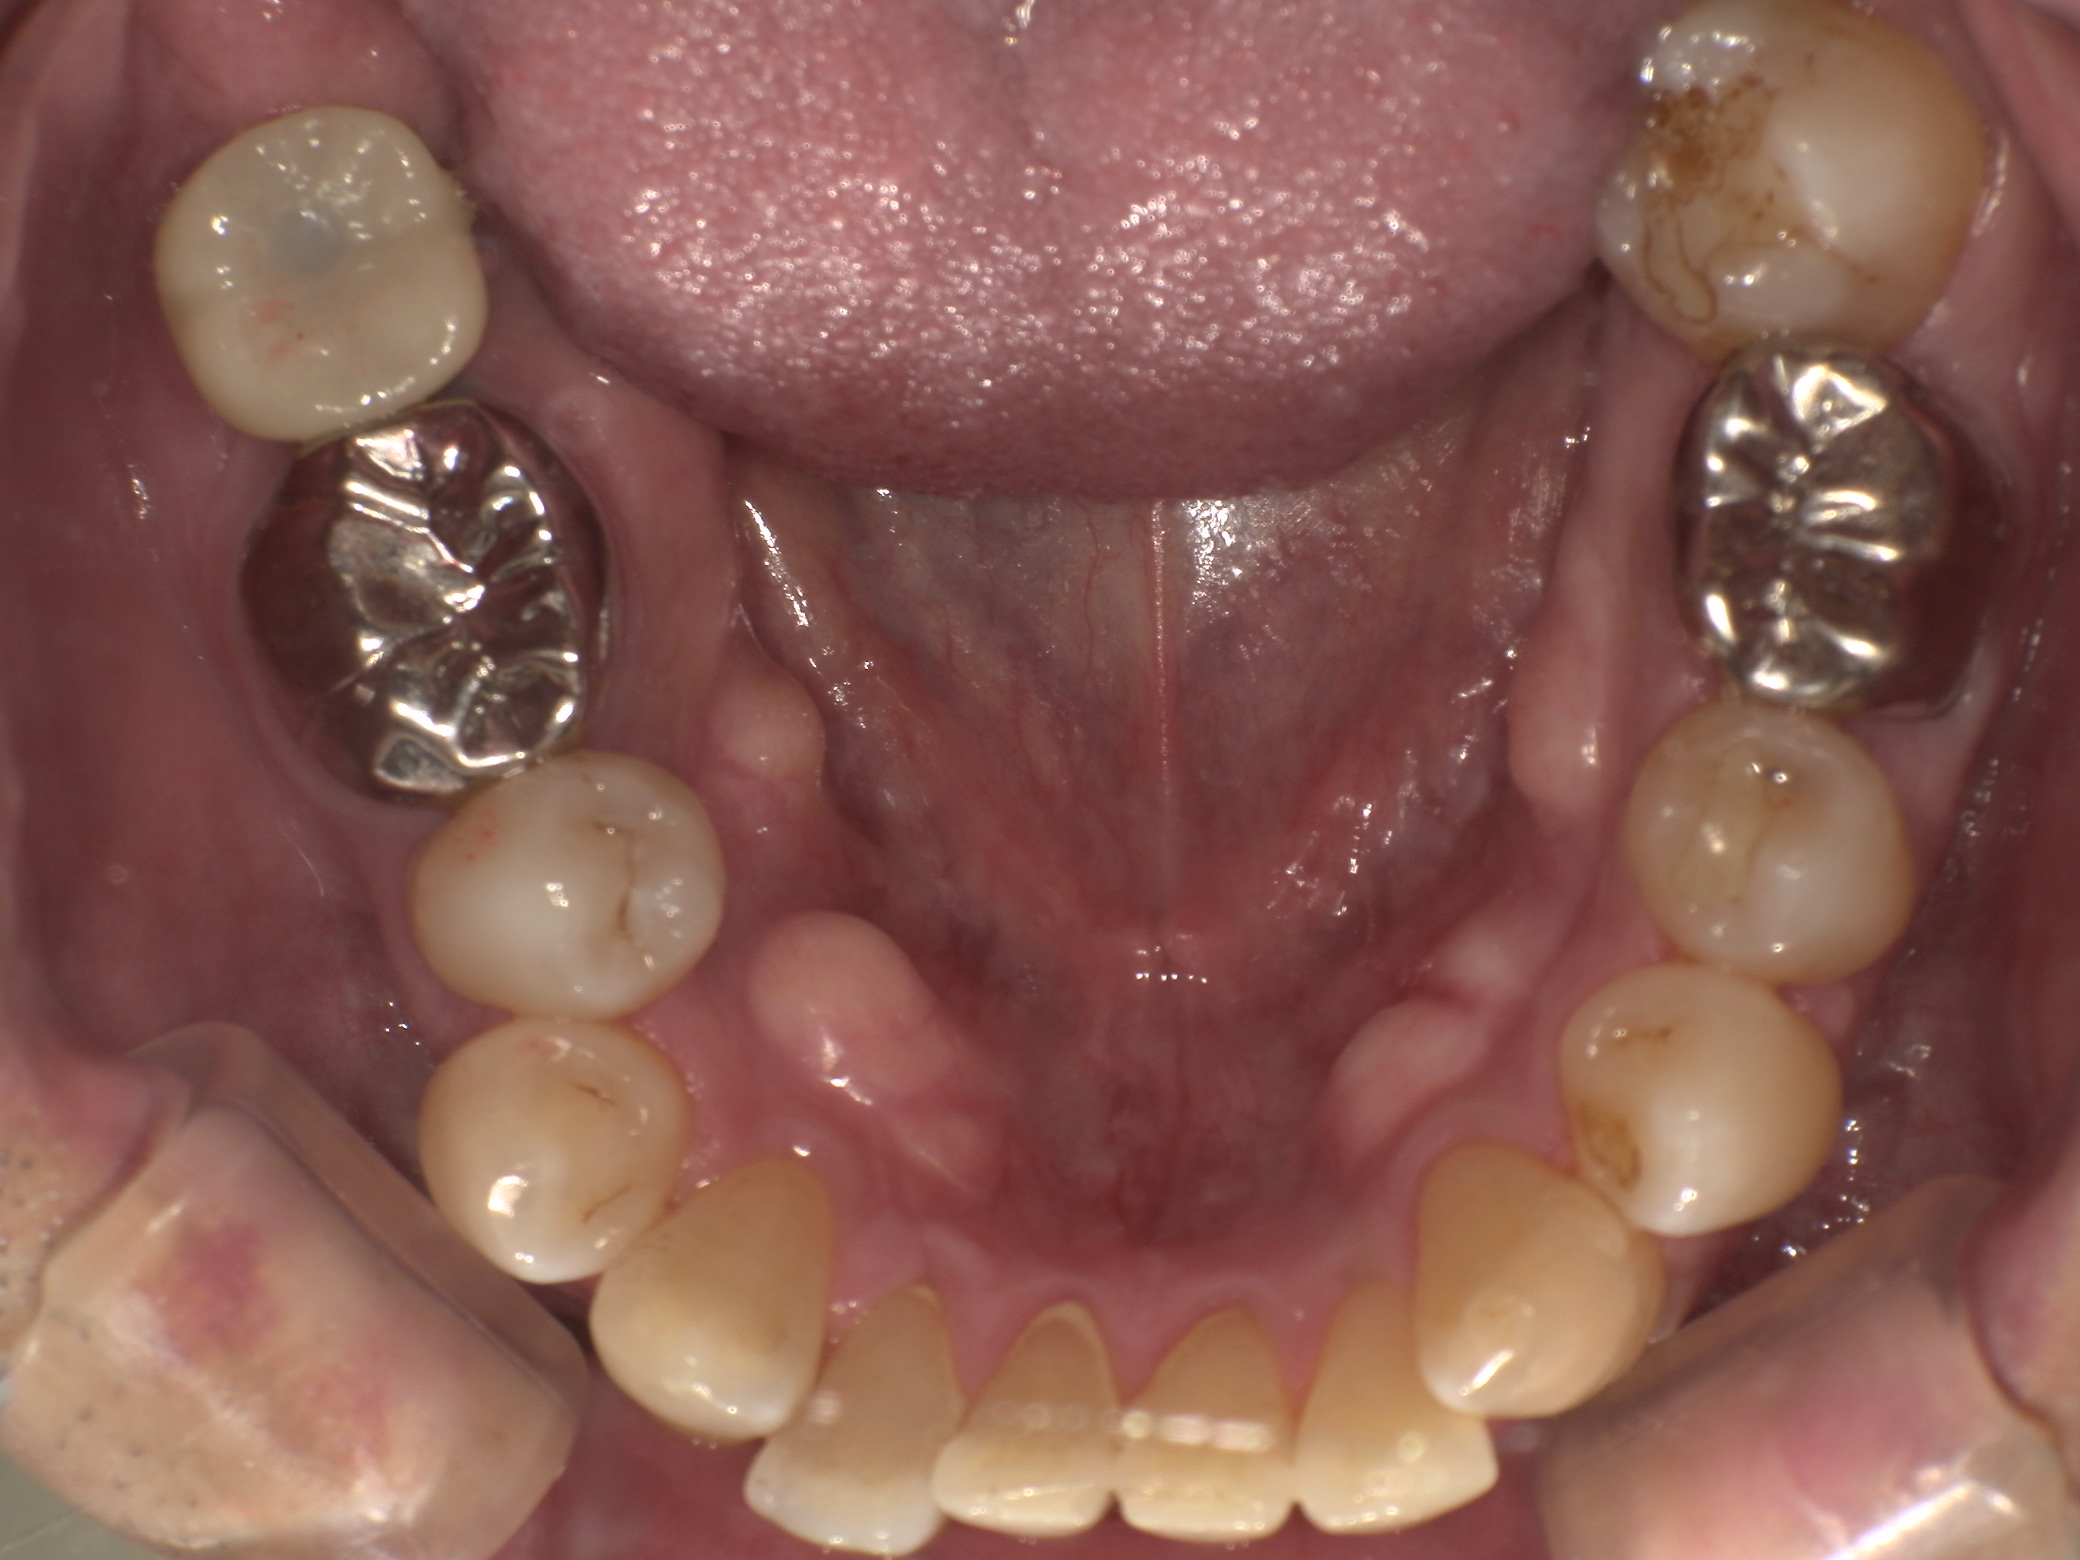

Before

右下の奥歯が重度の歯周病による骨の吸収も進み始めていました。また、痛みを伴うようになってきたため、残念ながら抜歯となり、インプラントによる治療を行うこととなりました。